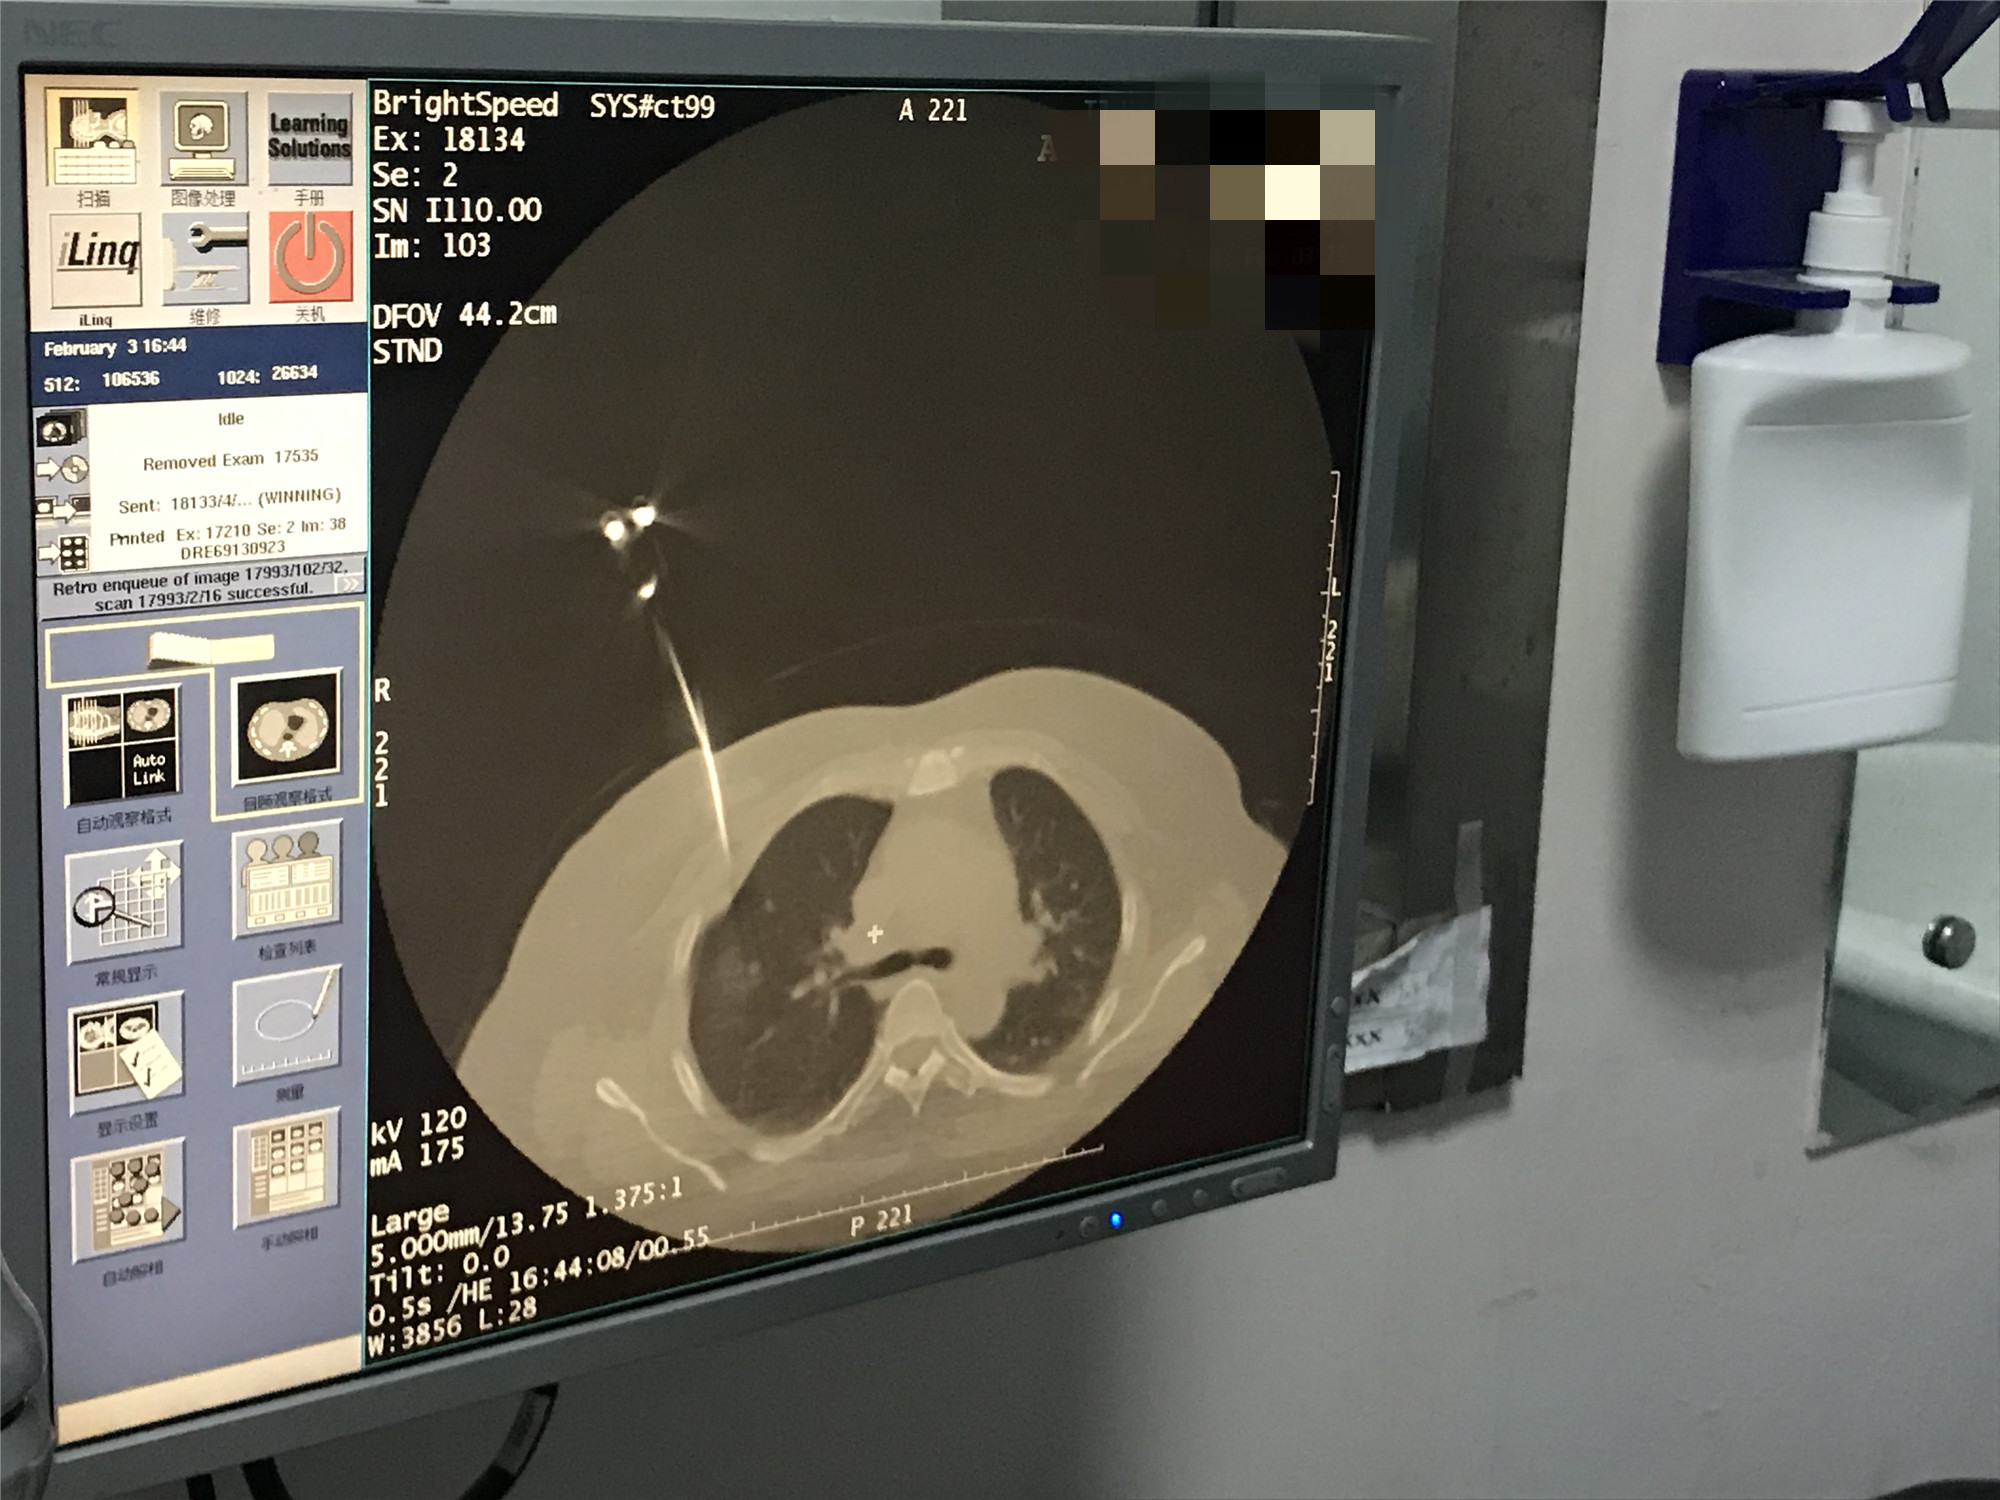

2021年2月份肺部氩氦刀手术

发布人:美国氩氦刀技术官方网站    发布时间:2021/9/22 15:42:38